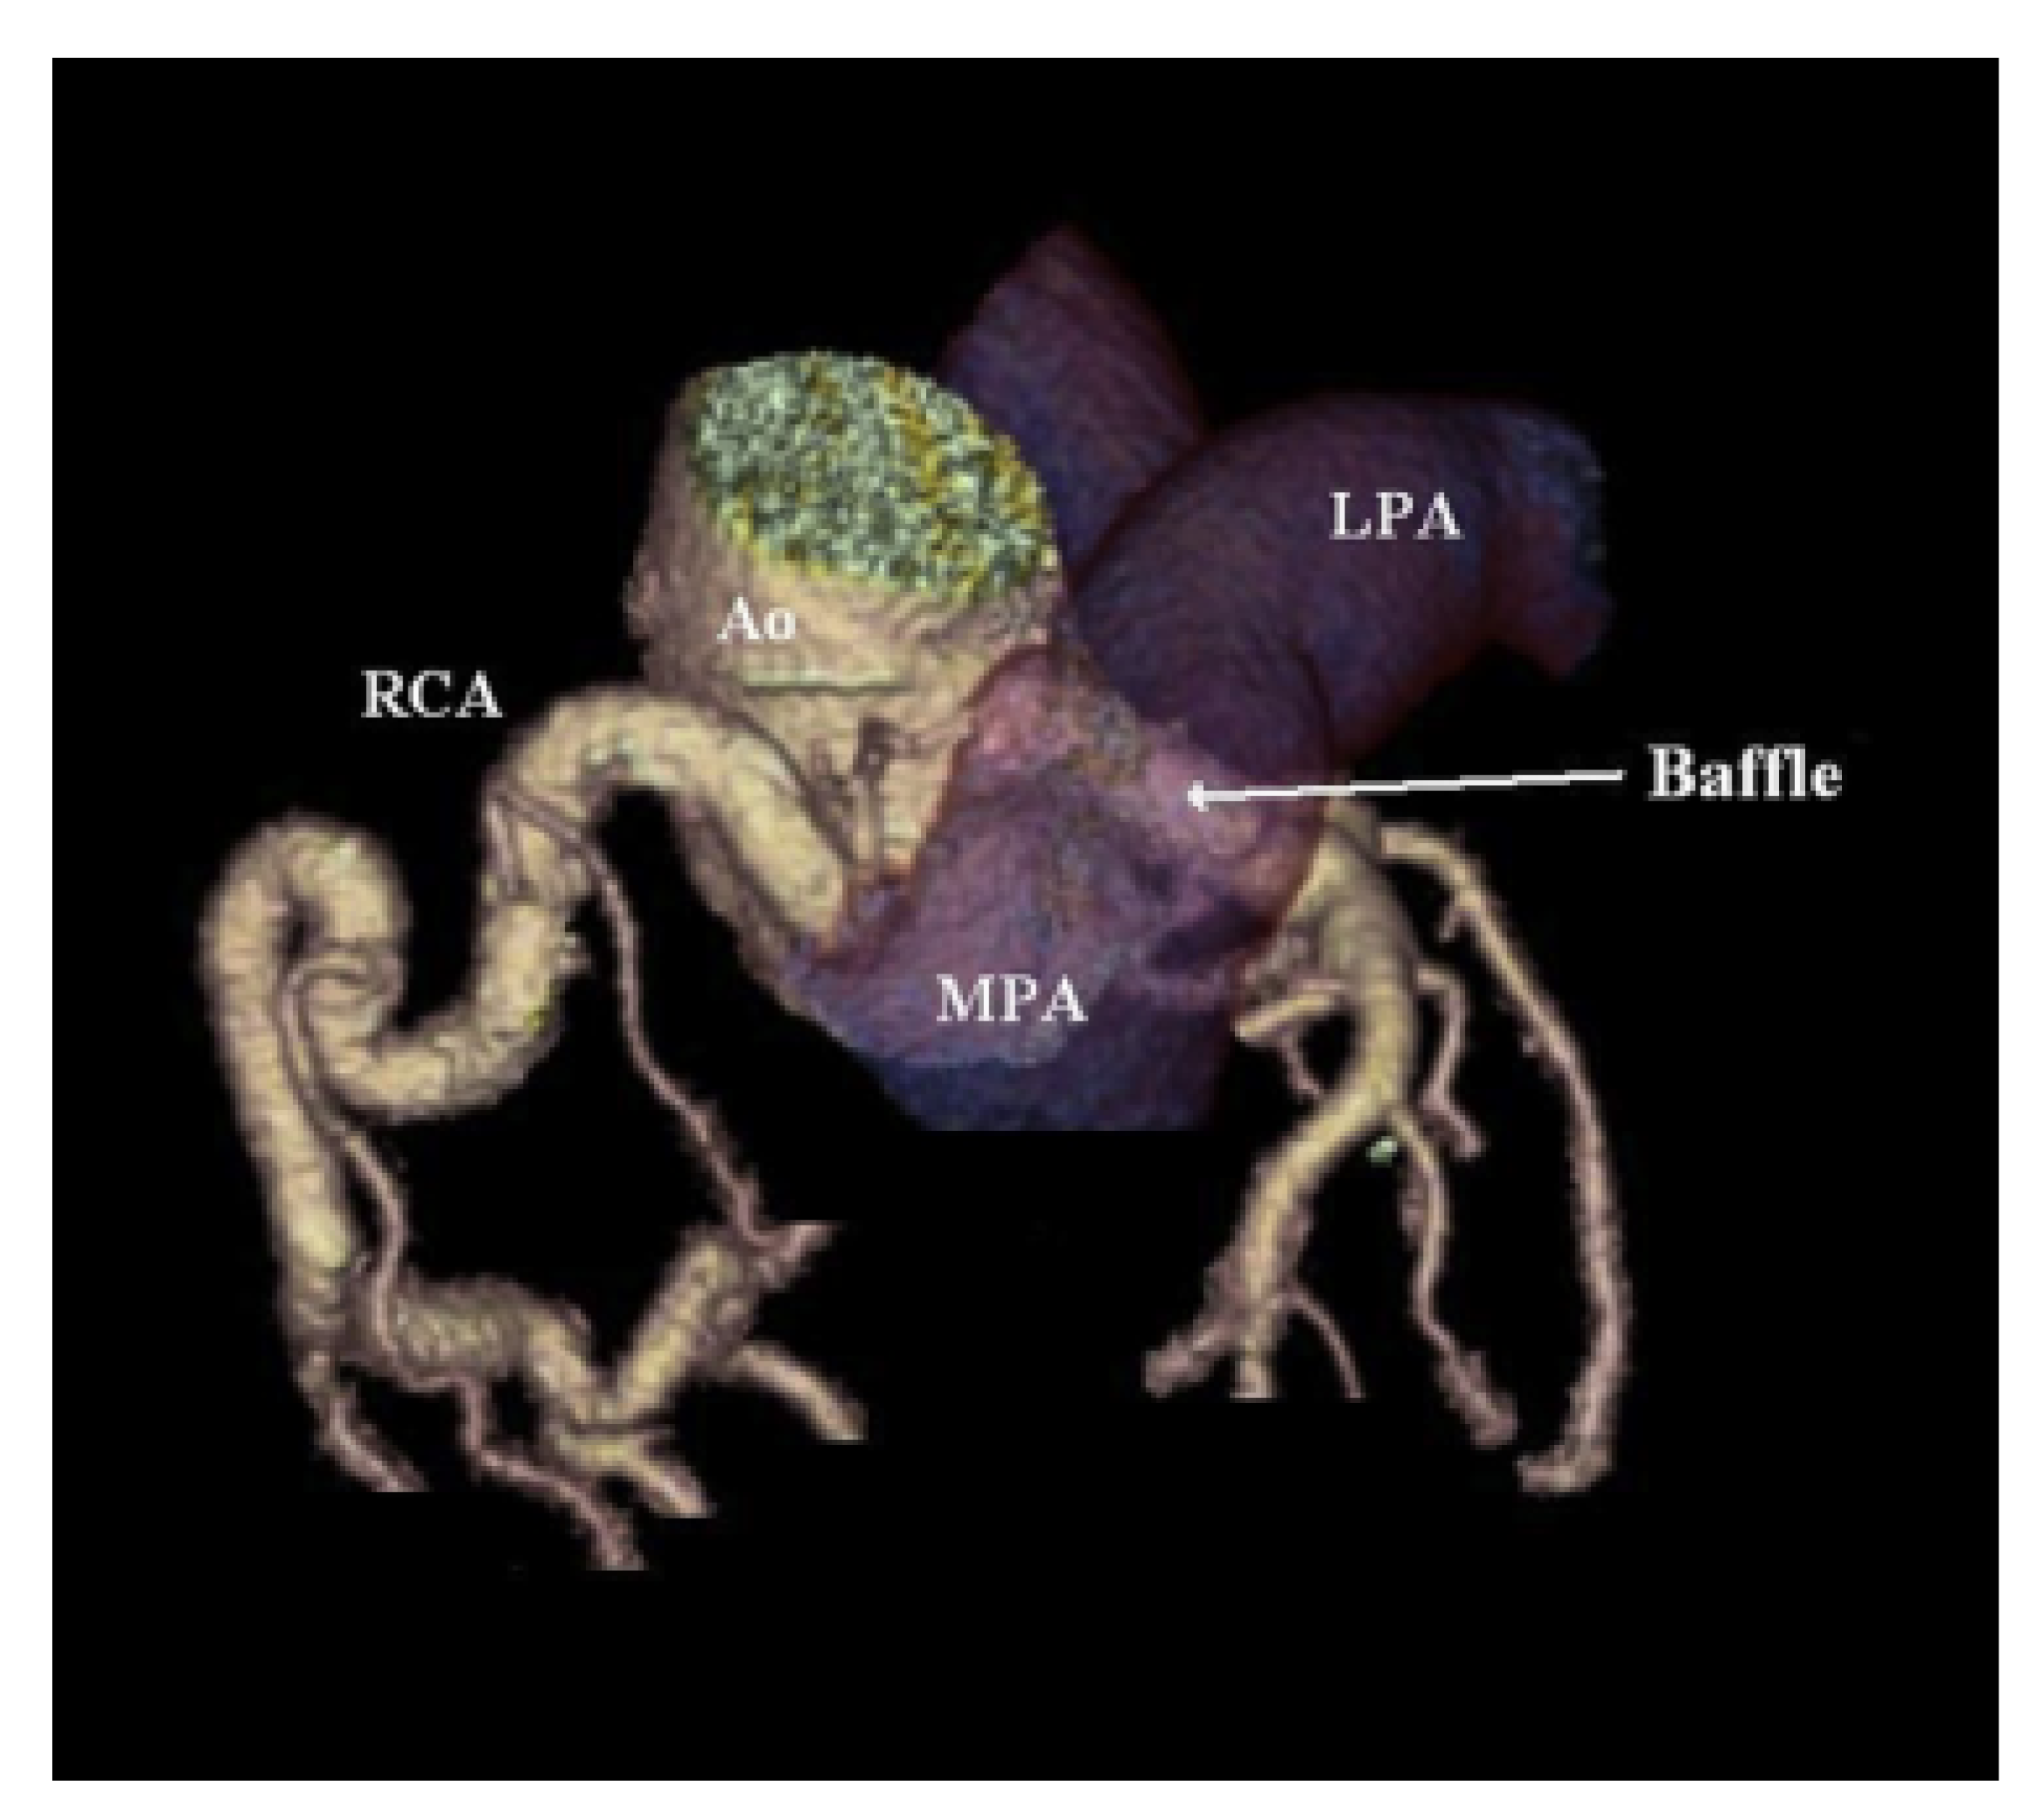

The Takeuchi technique requires the creation of an intrapulmonary baffle to connect the anomalous left coronary artery and aorta. An aortopulmonary window is made first; then, the baffle is constructed by suturing an anterior pulmonary flap to the posterior wall of the pulmonary artery. The pulmonary artery is then repaired with a pericardial patch (Figure 8) [15].

Direct reimplantation and its modifications have few complications in infants, but in adults, left coronary artery tearing and bleeding can occur due to the friability of the left coronary artery and diminished elasticity when the anomalous coronary is mobilized for repair [7]. The Takeuchi technique can lead to supravalvular pulmonary stenosis due to pulmonary artery manipulation, tissue resection, baffle leaks causing coronary–pulmonary artery fistula, baffle obstruction, and aortic regurgitation [25]. In the Ginde et al. series of nine patients who underwent Takeuchi repair for ALCAPA, all eight surviving patients had some degree of main pulmonary artery stenosis, with moderate stenosis in two patients and severe stenosis in one patient. Moreover, three late survivors had a baffle leak [26]. Pulmonary artery stenosis can lead to the need for additional future interventions, including surgery or transcatheter procedures. Coronary artery bypass grafting, which is considered the preferred method in adults, is also generally well-tolerated but has been associated with graft occlusion and stenosis [7].

Figure 8. Three-dimensional-reconstructed image from coronary computed tomography angiogram demonstrating intrapulmonary baffle following Takeuchi repair method. Used with permission from Cramer, J.W.; Cinquegrani, M.; Cohen, S.B. Takeuchi repair of anomalous left coronary artery from the pulmonary artery. J Cardiovasc. Comput. Tomogr. 2015, 9, 457–458. [22].